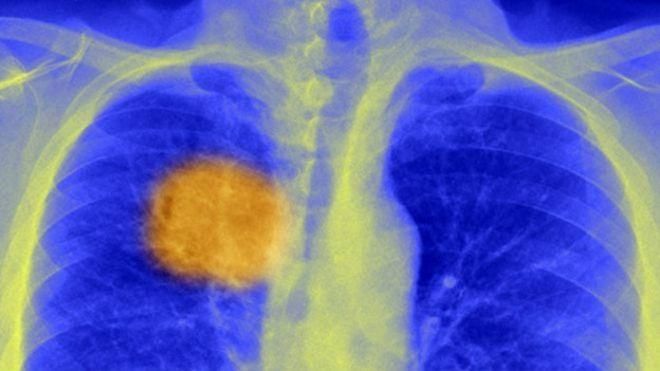

Імунну систему залучали для боротьби з онкозахворюваннями і раніше, але здебільшого всі відомі вакцини проти раку виявилися неефективними. Вчені з Університетського коледжу пояснюють це тим, що захисні механізми організму прямували на невірні цілі. Справа в тому, що ракова пухлина – це не єдине, рівномірне утворення. Вона складається з абсолютно різних, по-різному мутованих клітин, тому і поводитися окремі ділянки пухлини можуть по-різному.